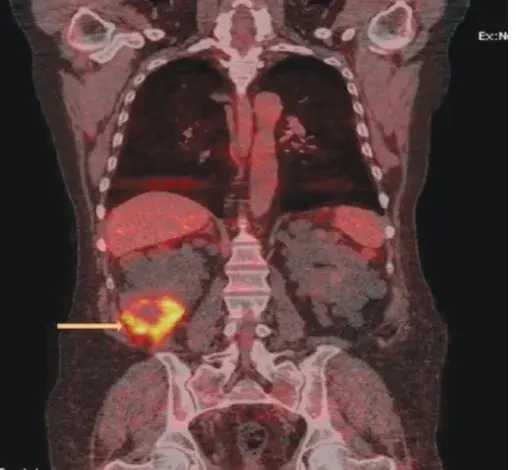

**Exames imagem**

- A ultrassonografia mostrou rins bilaterais de 10,6 cm com ecogenicidade cortical normal.

- A tomografia computadorizada não demonstrou nefrolitíase, mas mostrou linfonodos aumentados no retroperitônio, pelve, região hilar à direita, mediastino, axila esquerda e área retropeitoral. Opacidades pulmonares em vidro fosco também foram observadas.

A doença relacionada à IgG4 é uma condição imunomediada que pode causar lesões fibroinflamatórias em qualquer órgão, inclusive os rins. A apresentação clínica é muito variável, incluindo envolvimento de múltiplos órgãos, podendo **simular malignidade**, **infecção** e **doenças reumatológicas**.

Os exames de sangue podem mostrar **consumo de complemento** e **níveis elevados de IgG4**. Achados radiológicos como “pâncreas em salsicha”, periaortite infrarrenal e massas pulmonares e renais são fortemente sugestivos de doença por IgG4.

Os rins podem ser acometidos com massas, linfadenopatia retroperitoneal (causando obstrução) e nefrite tubulointersticial.